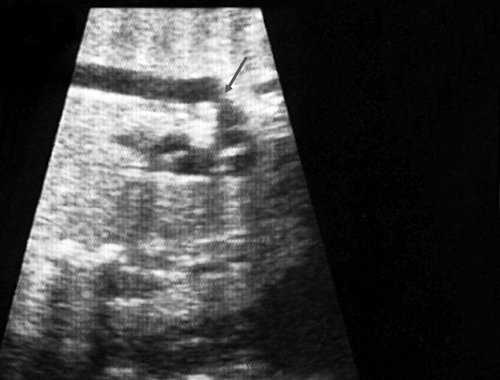

Рис. 2. Ультразвуковое исследование восходящего отдела, дуги и нисходящего отдела аорты. Стрелкой указано место сужения.

Рис. 3. Трехмерное изображение сердца и аорты плода в 16 нед беременности. Стрелкой указано место сужения аорты. AO DESC - нисходящий отдел аорты, COR - сердце.

Известно, что диагноз данного порока сердца опирается на прямой признак - визуализацию места сужения аорты, и, возможно, расширение проксимального отдела аорты. Однако четко визуализировать участок сужения аорты у плода достаточно трудно и удается только в единичных наблюдениях. Порок можно увидеть лишь тогда, когда имеется уменьшение диаметра перешейка аорты более чем на 1/3 по сравнению с нормой для каждого срока беременности (см. рис. 2, 3).